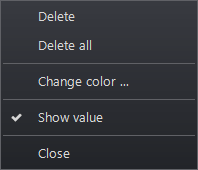

Modifying or Removing Annotations

To delete or modify an annotation:

-

Hover over annotation until icon appears and annotation is highlighted.

-

Right click on the image annotation

In the box that opens there are two options: Delete or Delete All. The other options allow modifications, including color and font changes, depending on the annotation.